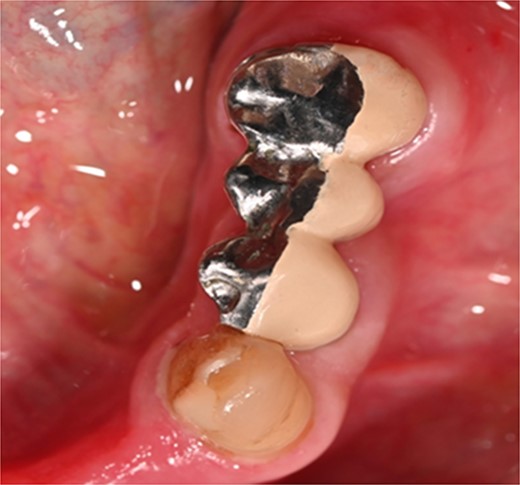

A 59-year-old male patient presented with a complaint of pain while biting on his lower left posterior teeth. Clinical examination revealed an extensive amalgam restoration on the lower left first molar (tooth 36) with a fractured restoration and secondary caries on the lingual aspect. The tooth was non-responsive to thermal testing and electrical pulp sensibility testing (EPT) and was tender to percussion. Radiographic examination showed radiolucency beneath the restoration on the mesial root surface, indicative of caries, along with furcation involvement and peri-radicular radiolucency. The tooth was diagnosed with pulpal necrosis and symptomatic apical periodontitis associated with extensive root caries (Fig. 6 and 7).

Clinical photograph of tooth 36 showing extensive amalgam restoration on mesio-occlusal-disto-bucco-lingual (MODBL).